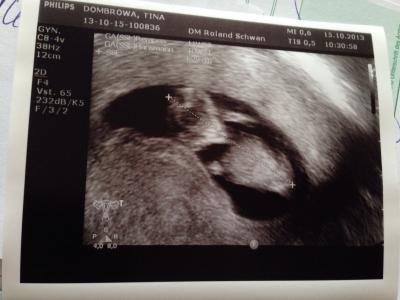

Guten Morgen, War gestern wegen ständiger Krämpfe beim Fa und es war so toll. Er hat sich für mich soviel zeit genommen und ich fühlte mich so gut aufgehoben. Meine große Tochter (6) durfte mit Baby schauen am Kopf und es war so spannend für uns beide. Er hat der kleinen alles genau erklärt und sie war happy. Habe letztendlich ein BV bekommen und ich bin froh und erleichtert und kann es jetzt anfangen zugebissen - vorausgesetzt die Übelkeit verabschiedet sich langsam. Beste Grüße an euch alle... Anbei noch unser Mini :-))) ganz klein, aber am zappeln und Herzchen hat schön gepochert.

Bild zu FA gestern - Forum für Mai - Mamis